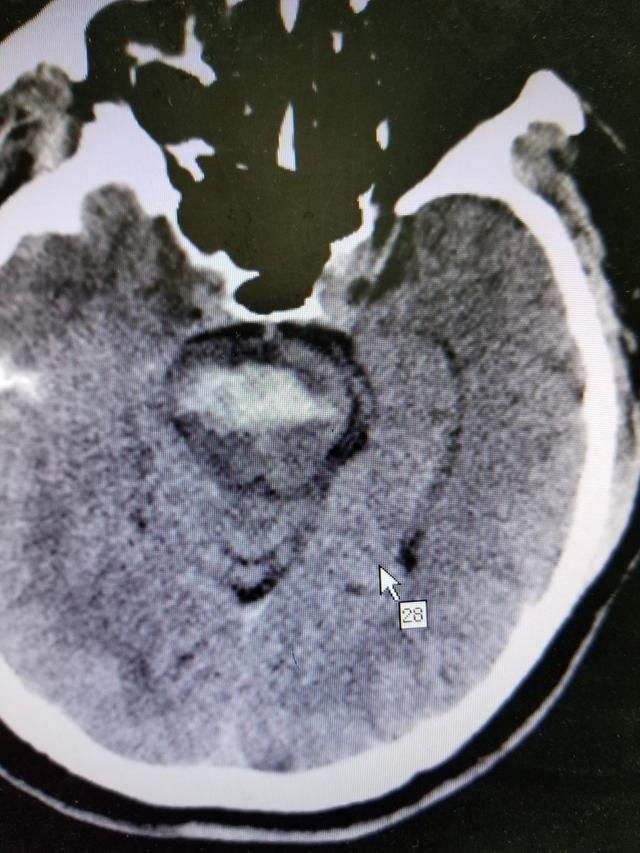

患者被紧急送到医院确诊为脑干出血,患者的呼吸和心率已经受到影响。

医生一看问的比较专业,因为人脑分为大脑、小脑和脑干;脑干又是由三个部分组成,中脑、脑桥和延髓。

医生告诉患者的儿子:“主要的出血部位是脑干的延髓。”

脑干出血非常凶险,特别是延髓部位的,因为这里有呼吸循环中枢,出血后往往会导致患者的呼吸和心跳。

脑干出血的特点

6、该部位发生出血,即使微小的出血和血肿可引起严重的后果。其临床表现危重,易出现昏迷、中枢性呼吸循环衰竭、脑内脏综合征、脑疝、MODS等致命性并发症。

为啥脑干几毫升的血就昏迷了?

很多人都会问:脑干出血几毫升就昏迷,而有的人出血几十毫升还没什么事?

主要是因为这个出血的地方叫脑干:

1、脑是人最重要的器官,而脑干又是人脑中最重要的部位,管人的呼吸和心跳的地方就在这里,还有链接大脑与身体的重要传导通路。

2、脑干重要但占得地方却很小,大约自己大拇指这么粗,并且对外界影响反应剧烈,以前这里是脑科手术的禁区,现在很多水平高超的神经外科医生已经可以做脑干部位手术了。在手术过程中滴上一滴水病人呼吸和心跳都会有明显的变化。

3、相同量的脑出血,出血部位不同,对身体身体的影响和处置方式完全不同 。

在大脑半球一般30毫升以下都不用手术,在小脑10毫升以上就要手术了。但脑干出血一般很少手术,因为位置太重要,手术难度大,手术后可能损伤更大。

4、脑干并不是一个部位,它包括中脑,脑桥,延髓三部分,不同部位出血症状是不一样的,但这些地方都很重要,一般如果出血5毫升以上就算出血量大的,预后相对较差。